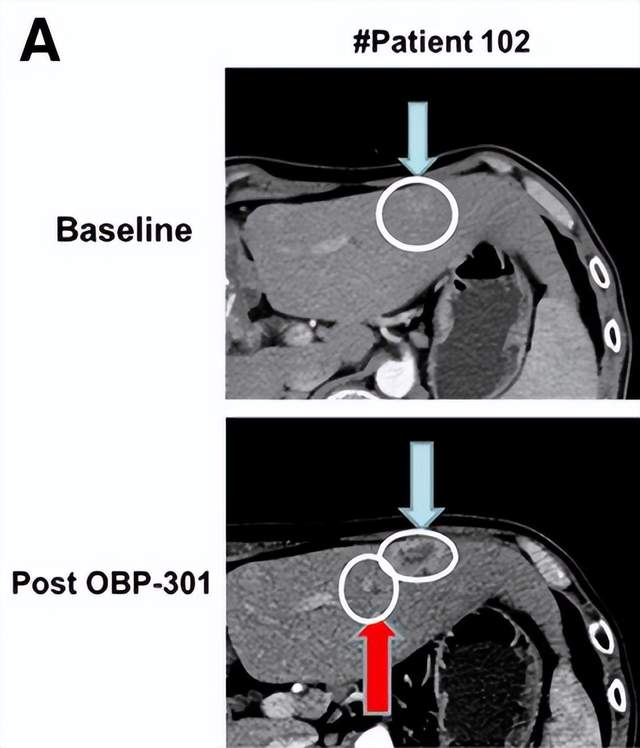

OBP-301不仅在食管癌具有治疗潜力,在肝癌治疗中同样产生一定的疗效。在2023年公布的一项OBP-301治疗难治性晚期肝癌的I 期临床试验中,一名49岁男性曾因门静脉肿瘤血栓和肺转移接受过14次经动脉化疗栓塞(TACE)、放射治疗以及索拉非尼治疗,但由于索拉非尼引发的治疗中出现的不良事件(TEAEs),他拒绝接受二线靶向治疗。在注射OBP-301后,该病灶显示出明确的坏死表现。

一名57岁男性,患有门静脉肿瘤血栓,曾接受过13次TACE、放疗及索拉非尼治疗。该患者因不愿接受二线靶向治疗而参与本研究。在三次OBP-301注射后,观察到显著的肿瘤坏死。